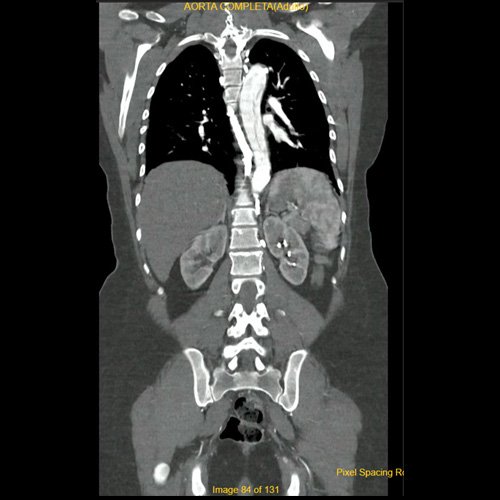

Angiotomografía con contraste endovenoso de aorta torácica. Corte axial.

• Angio-TCMS de aorta toracoabdominal y vasos iliofemorales - pre informe (día 0): Interpretación: Se identifica un flap de disección aórtica, que se extiende desde la raíz aórtica, hasta el segmento distal de la aorta torácica descendente, asociado a dilatación aneurismática de la raíz aórtica y la aorta ascendente. No se observa disección de aorta abdominal al momento del examen. El flap de disección compromete la aorta ascendente, el arco aórtico y los tres vasos supraaórticos, extendiéndose hacia el tronco braquiocefálico derecho, con compromiso de la arteria subclavia derecha, así como también de la porción proximal de la arteria carótida primitiva izquierda y de la arteria subclavia izquierda. No impresiona compromiso de la emergencia de las arterias coronarias por esta metodología. Diámetros de la Aorta en sus diferentes porciones:  Senos de Valsalva: 40 mm.  Región media de aorta ascendente: 37 mm. Región media del cayado: 23 mm. Región media de la aorta descendente: 22 mm. A nivel de las cruras diafragmáticas: 19 mm. A nivel del origen del tronco celíaco: 18 mm. A nivel infrarrenal: 14 mm. Previo a su bifurcación iliaca: 13 mm. Hipertrofia del ventrículo izquierdo. Derrame pericárdico de 13 mm de espesor a nivel de cara anterior, de densidad promedio de 30 UH. El esófago es de calibre y trayecto normales. El mediastino está en posición central. No se observan adenomegalias mediastinales, axilares o hiliares. El árbol traqueobronquial no presenta alteraciones. Áreas de aneumatosis bibasal. No se observa derrame pleural. El hígado es de forma, tamaño y situación habituales. Su superficie es lisa, y sus bordes son agudos. El parénquima hepático presenta atenuación heterogénea, con áreas hipodensas difusas, hallazgos que podrían estar en relación con trastorno perfusional. Se observa además edema periportal. La vía biliar intra y extrahepática es de calibre conservado. La vesícula biliar es de forma, tamaño y situación normales, sin imágenes que sugieran la presencia de litiasis. Tener en cuenta que este método puede pasar por alto litiasis colesterínicas. Edema perivesicular. El bazo es de forma, tamaño y situación normales. El eje esplenoportal es de calibre y trayecto conservado, permeable. El páncreas es de características normales. El conducto de Wirsung es de calibre conservado. Las glándulas adrenales son normales. Ambos riñones son de forma, tamaño y situación habituales. Concentran y eliminan normalmente la sustancia de contraste, sin evidencia de alteraciones calicopiélicas ni ureterales. La vena cava inferior y las venas ilíacas primitivas, internas, externas y femorales son de calibre y trayecto conservados, permeables. No se observan adenomegalias intraperitoneales, retroperitoneales, ilíacas ni inguinales. No se observan alteraciones a nivel del tracto gastrointestinal. Vejiga con escasa repleción, con sonda balón en su interior. El útero es de forma, tamaño y situación conservada, sin alteraciones densitométricas, en anteversoflexión. En topografía de ambos anexos se observan colecciones líquidas de aspecto funcional que miden 23 mm a izquierda y 18 mm a derecha. Escasa cantidad de líquido libre en el fondo de saco de Douglas. Espondiloartrosis de la columna dorso-lumbar.